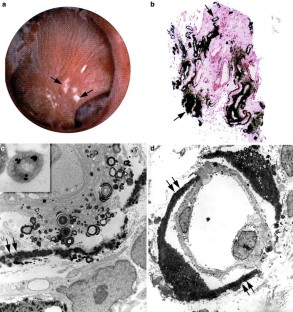

The purpose of these studies was to test the hypothesis that Randall’s plaque develops in unique anatomical sites of the kidney and that its formation is conditioned by specific stone-forming pathophysiologies. To test this hypothesis, we performed intraoperative mapping studies with biopsies of papilla from the kidneys of 15 idiopathic calcium oxalate (CaOx) stone formers, four intestinal bypass for obesity patients and ten brushite stone formers, and obtained papillary specimens from four non-stone formers after nephrectomy. Both light and electron microscopic examination of tissue changes along with infrared and electron diffraction analyses of mineral composition were performed. Distinct patterns of mineral deposition and papillary pathology were discovered in each of the three different stone forming groups. CaOx stone formers had predictable sites of interstitial apatite crystals beginning at the thin loops of Henle and spreading to the urothelium. These plaque areas are termed Randall’s plaque and are thought to serve as sites for stone attachment. The papilla and medullary tubules appeared normal. The intestinal bypass patients only had intraluminal sites of crystalline material in the medullary collecting ducts. The brushite stone formers had the most severe form of cortical and medullary changes with sites of Randall’s plaque, and yellowish intraluminal deposits in medullary collecting ducts. All deposits were determined to be apatite. The metabolic and surgical pathologic finding in three distinct groups of stone formers clearly shows that “the histology of the renal papilla from a stone former is particular to the clinical setting”. It is observations like these that we believe will provide the insights to allow the stone community to generate better clinical treatments for kidney stone disease, as we understand the pathogenesis of stone formation for each type of stone former.

Fig. 1

Fig. 2

Fig. 3